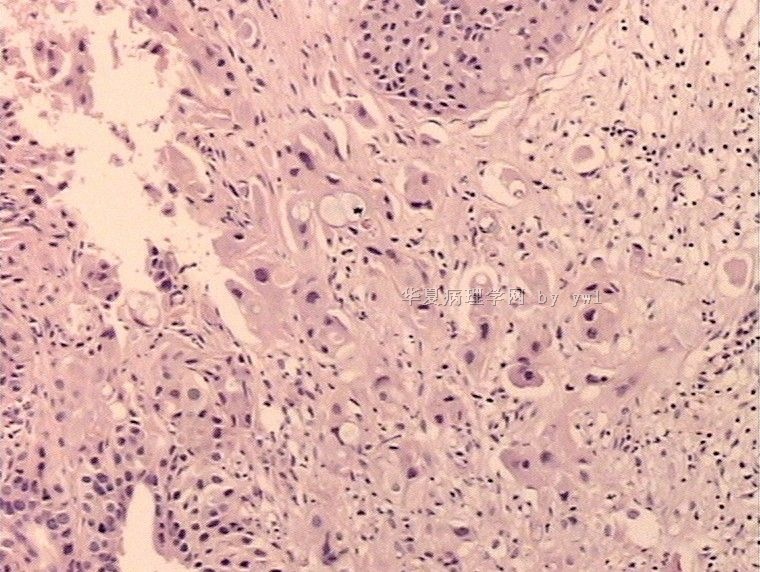

腺鳞癌?

姓    名: ××× 性别:   年龄:  39岁

标本名称:  宫颈活检

简要病史:  同房出血3次,tct HSIL

考虑:原位腺癌,小灶性区域有鳞状上皮向间质内浸润,考虑有鳞状细胞癌结构。

• 腺鳞癌?图1

图1